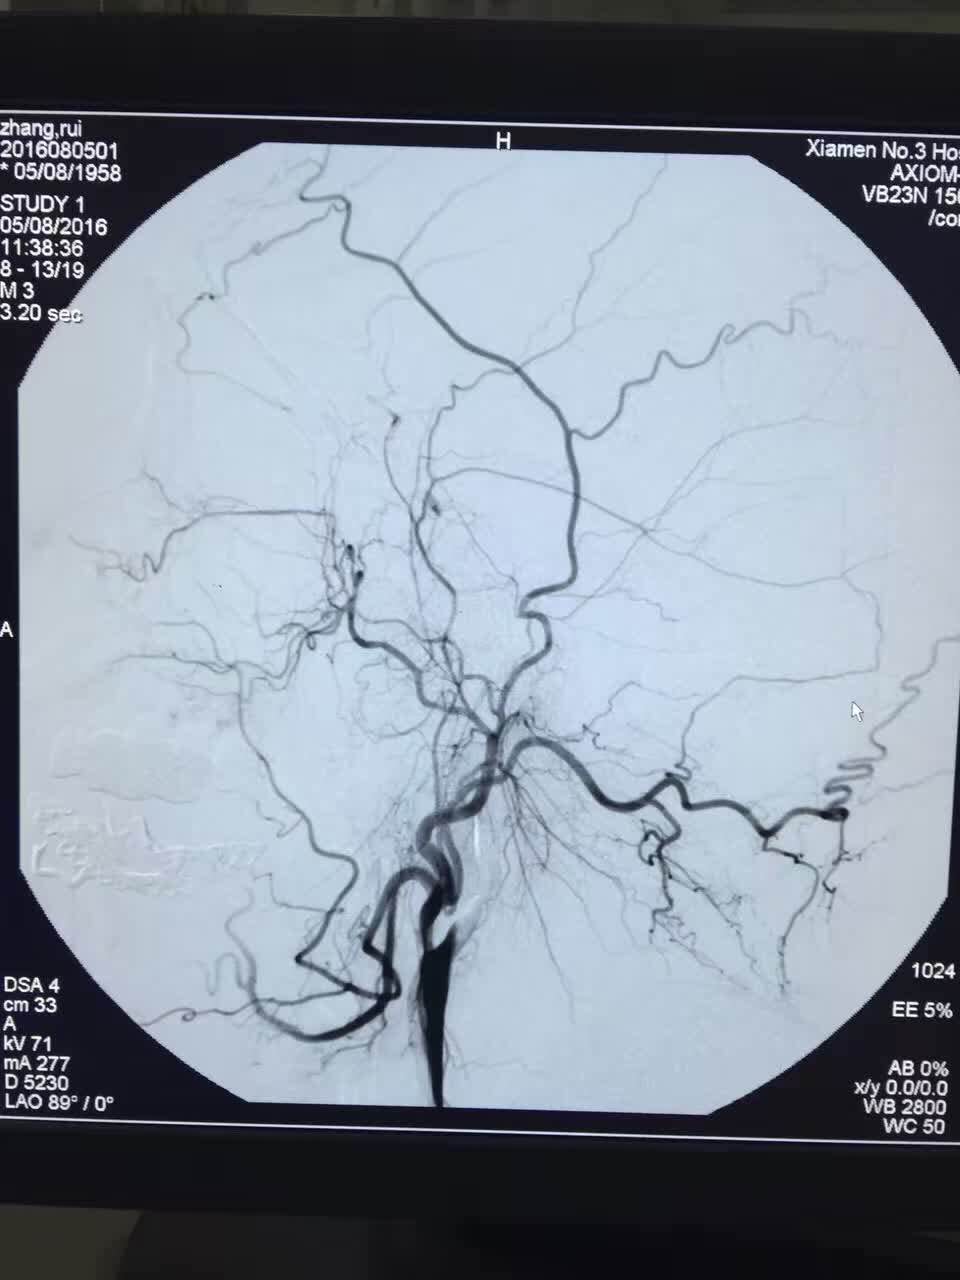

影像科为王先生行核磁共振检查,发现王先生脑左侧颈内动脉延伸至大脑中动脉已经完全被堵塞,专家组综合分析,判断是心衰引起的心源性脑栓塞。叶惠龙院长指示:立即采用目前国际前沿的微创脑血栓取栓术。患者立即被送到导管室,神经内科、介入组、导管室、重症医学科、麻醉科等多学科抢救组的专家也同时全部到位。由于患者有严重的高血压心脏病,心脏极度肿大,胀大至原来的两倍多,却收缩弱,导管尚未进入时病人就已经出现严重的心衰、房颤,心血管内科组及时予以抗心衰、药物及电击除颤等处理,待病情稍微稳定后介入组就立即插入导管取栓。